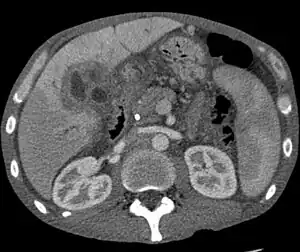

| CT scan of a liver with cholangiocarcinoma | |